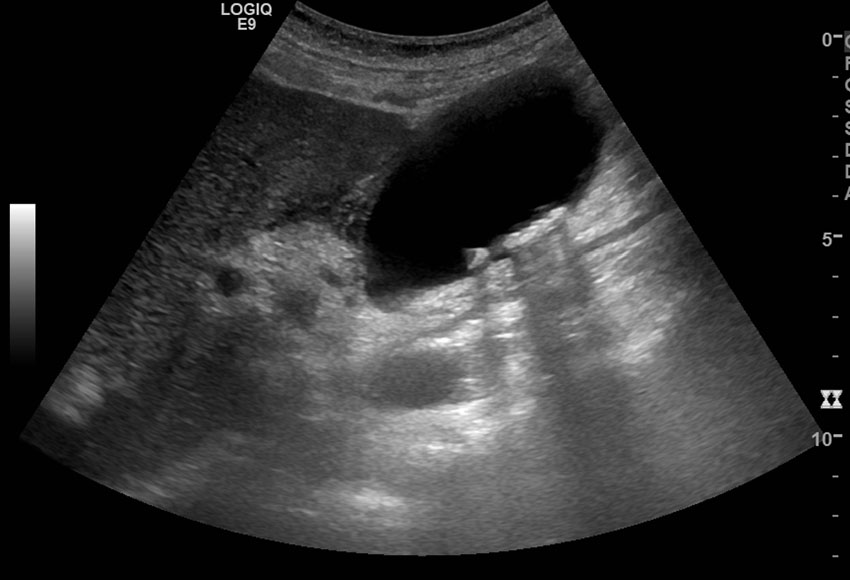

Cholezystolithiasis mit Cholezystitis

In der heutigen Zeit zählt die Sonographie zu den fundamentalen diagnostischen Verfahren und kann in den Händen von geübten Anwendern eine beträchtliche Anzahl von Erkrankungen ein- oder ausschließen. Wie ein Stethoskop sollte die Sonographie als ein Werkzeug des praktizierenden Arztes verstanden werden, dessen er sich bedienen kann, um seinen Patienten eine optimale Behandlung zukommen zu lassen. Gerade die Abdomensonographie bietet als erste bildgebende Untersuchung bei unklaren Bauchschmerzen, Verdacht auf Organpathologien oder zur Verlaufskontrolle bekannter Erkrankungen einen unschätzbaren diagnostischen Mehrwert.